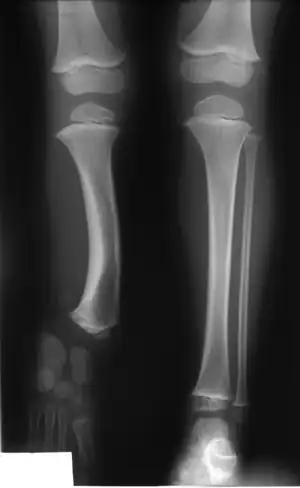

| Radiographic presentation of child with fibular hemimelia type II | |